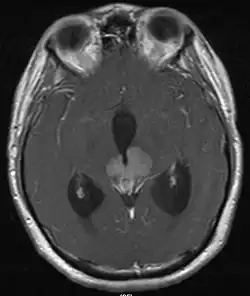

• Mainly located in midline structures, suprasellar region or pineal gland, also basal ganglia and hypothalamus

• Natural spread believed to be along subependymal lining of 3rd and 4th ventricles, leading to intraventricular relapse before spinal dissemination

Location